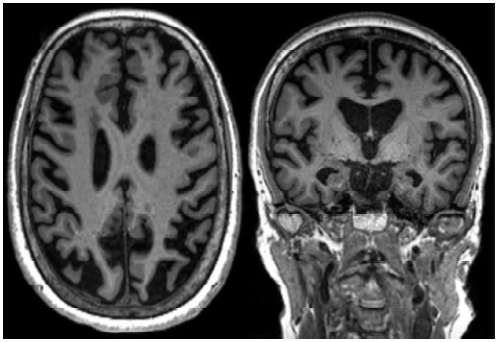

A atrofia da porção mesial do lobo temporal é frequente na Demência por Doença de Alzheimer (DA). A escala analógica visual MTA (mesial temporal atrophy), consegue avaliar a presença da atrofia mesial, e é classificada em números considerando a espessura da fissura coroidea e do corno temporal e a altura do hipocampo, e tem sensibilidade e especificidade de cerca de 85% para o diagnóstico de DA. Analise a imagem de ressonância abaixo.

Pode-se considerar que a imagem da ressonância acima, corresponde a qual número MTA?